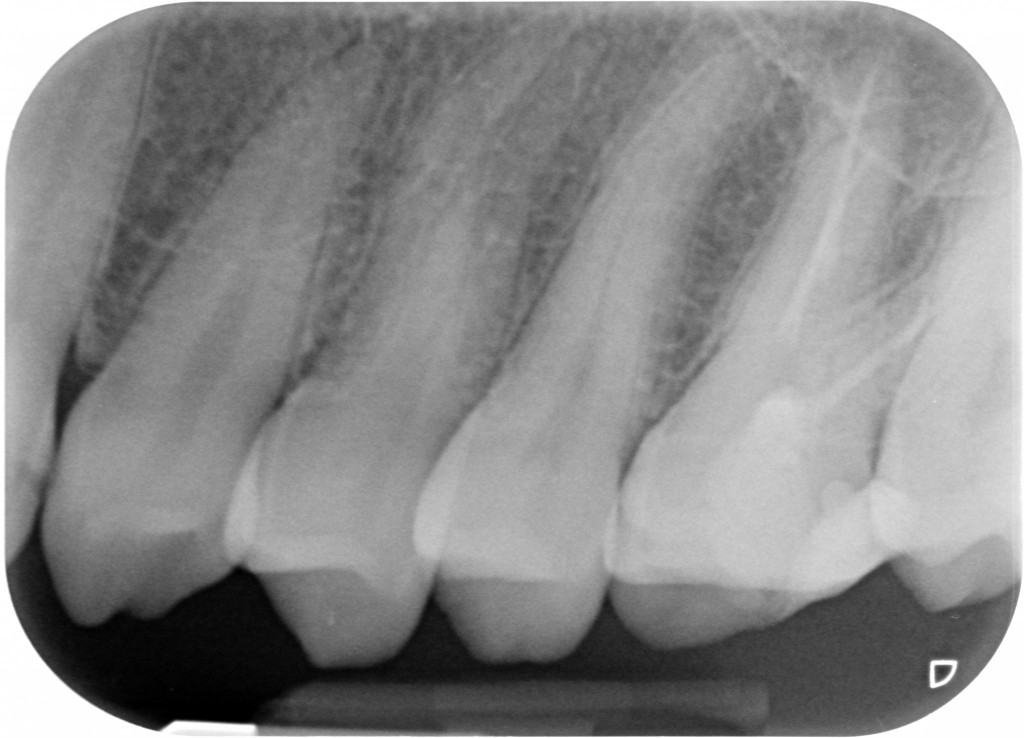

Comincio a fare una periapicale in alto a sinistra. Non centro bene la lastra e mi esce fuori questo.

Bah, potevo anche dedicare 10 secondi in più a centrare meglio…cmq quel che mi serviva lo vedo e cioè: NESSUNA CARIONA, SE NON UNA D1 SU 23, NESSUNA OTTURAZIONE ENORME A CONTATTO COL NERVO DI UN DENTE VIVO E UN DENTE DEVITALIZZATO CHE ANCHE SE CENTRATO MALE E PROBABILMENTE SENZA CANALE MV2 TROVATO NON MOSTRA GROSSE LESIONI PERIAPICALI.

Bah, potevo anche dedicare 10 secondi in più a centrare meglio…cmq quel che mi serviva lo vedo e cioè: NESSUNA CARIONA, SE NON UNA D1 SU 23, NESSUNA OTTURAZIONE ENORME A CONTATTO COL NERVO DI UN DENTE VIVO E UN DENTE DEVITALIZZATO CHE ANCHE SE CENTRATO MALE E PROBABILMENTE SENZA CANALE MV2 TROVATO NON MOSTRA GROSSE LESIONI PERIAPICALI.

Perfetto, siamo al punto di partenza.

Faccio allora una bite wing, stavolta centrata un po’ meglio a prendere anche la parte distale del 27 che mancava nella rx precedente…